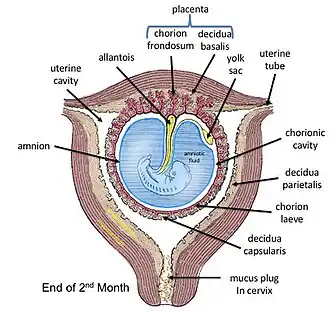

The amniotic sac consists of two parts:

- The outer membrane is the chorion. It is closest to the mother and physically supports the much thinner amnion.

- The chorion is the last and outermost of the membranes that make up the amniotic sac.[13]

- The inner membrane is the amnion. It is in direct contact with the amniotic fluid, which surrounds the fetus.